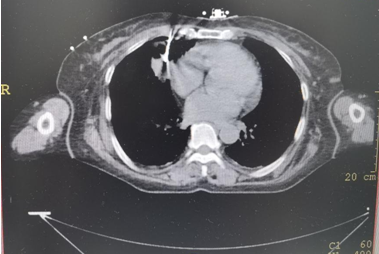

▲上图:穿刺到位

▲上图:肿瘤内科雷雨副主任医师在IQQA-Guide引导下实施肿瘤穿刺活检术